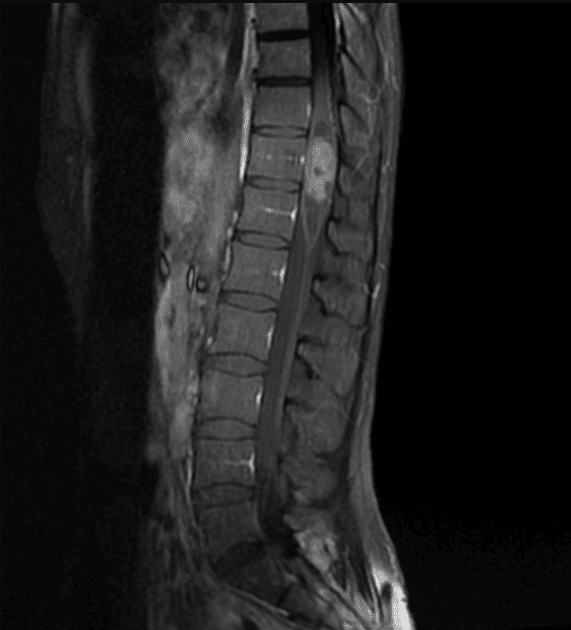

U màng nội tủy

» Thông tin: Nữ giới – 35 tuổi.

» Lâm sàng: Yếu chi dưới.

# U màng nội tủy nhầy nhú (Myxopapillary Ependymoma).